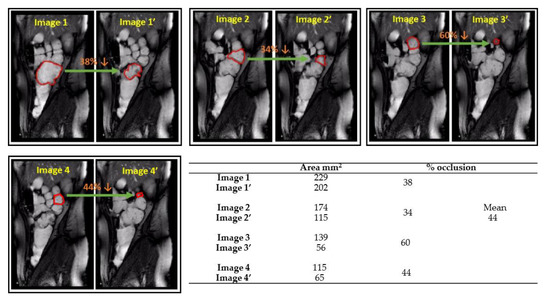

3.1. Determining Haustral Activity in the Cecum-Ascending Colon Using Cine-MRI